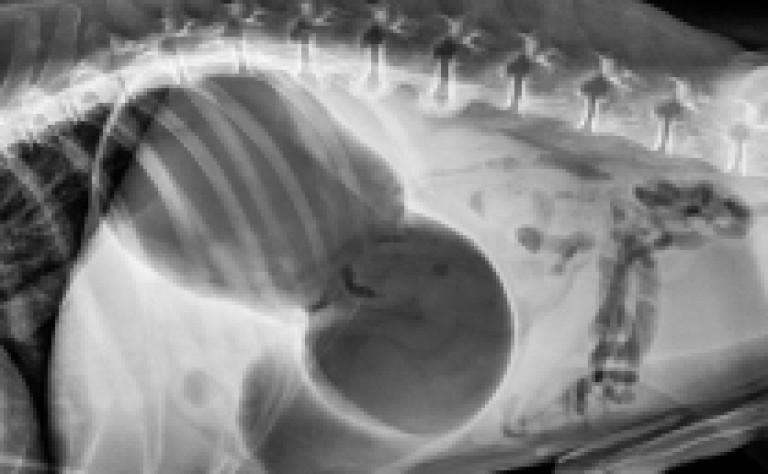

Finalement, le STDE est confirmé ou non grâce à une radio.

La torsion de l’estomac se produit lorsque l’estomac d’un chien se remplit de gaz, de fluide ou d'aliments et se tord sur lui-même.

Lors de la dilatation, l'estomac peut occuper plus de la moitié de la cavité abdominale !

La dilatation est très douloureuse et perturbe le fonctionnement des fonctions vitales telles que la respiration et la circulation du sang.

La torsion du tractus digestif empêche non seulement le gaz de s'échapper, mais il coupe également la circulation sanguine vers certains tissus.